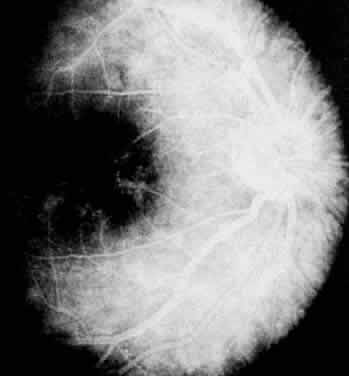

Fig. 5. Pars planitis. Fluorescein angiogram showing diffuse venous and capillary leakage.

FLUORESCEIN ANGIOGRAPHY AND VITREOUS FLUOROPHOTOMETRY

In pars planitis, fluorescein angiography shows diffuse leakage from the retinal venules and capillaries, without any predilection for the inferior retinal vasculature (Figs. 5 and 6).28 Similarly, vitreous fluorophotometry in patients with pars planitis also shows no predilection for vascular leakage in the inferior peripheral retina.29 These findings suggest that snowbank is most likely a sequela from ocular inflammation, that inferior peripheral retina periphery is not the source of inflammation in pars planitis, and that pars planitis is not a localized inflammatory response of the inferior retina.